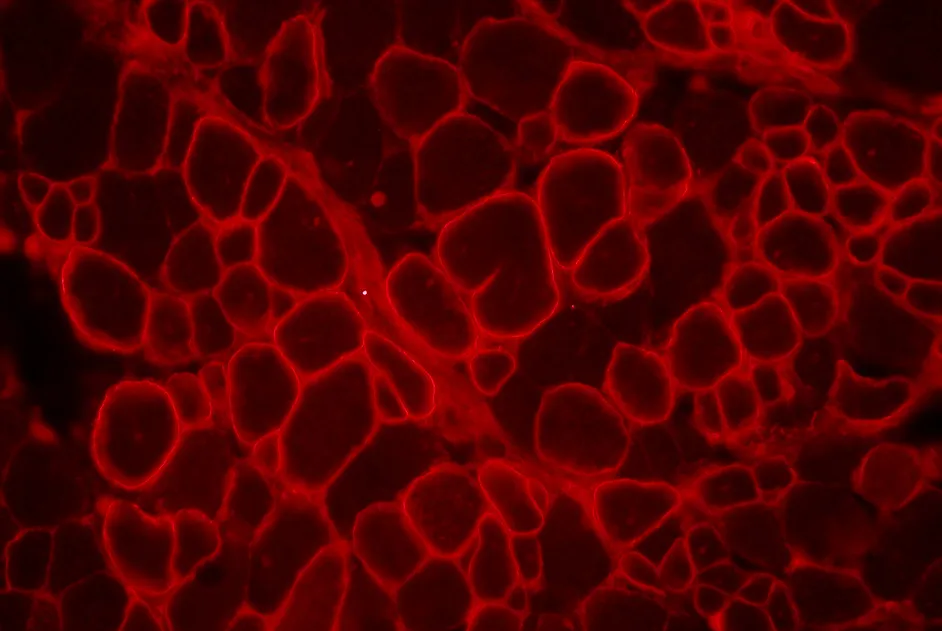

Une activation initiée par le gène DUX4 dans un noyau de fibre musculaire et qui se propage dans les noyaux voisins